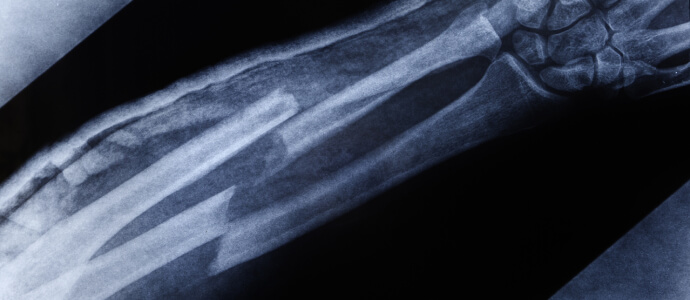

X-ray of broken bones in forearm

Your doctor will carefully examine you to see if there is evidence you’ve broken a bone. If there is, he or she will order an X-ray or CT scan to get a closer look. Broken bones need to be set (put back in their original position) and should be immobilized using a cast or some other type of physical restriction. You can expect your recovery to take 6-8 weeks, but the actual time will vary based on the nature of the injury, your age, and other factors. Your doctor will provide instructions on how to ensure proper healing.